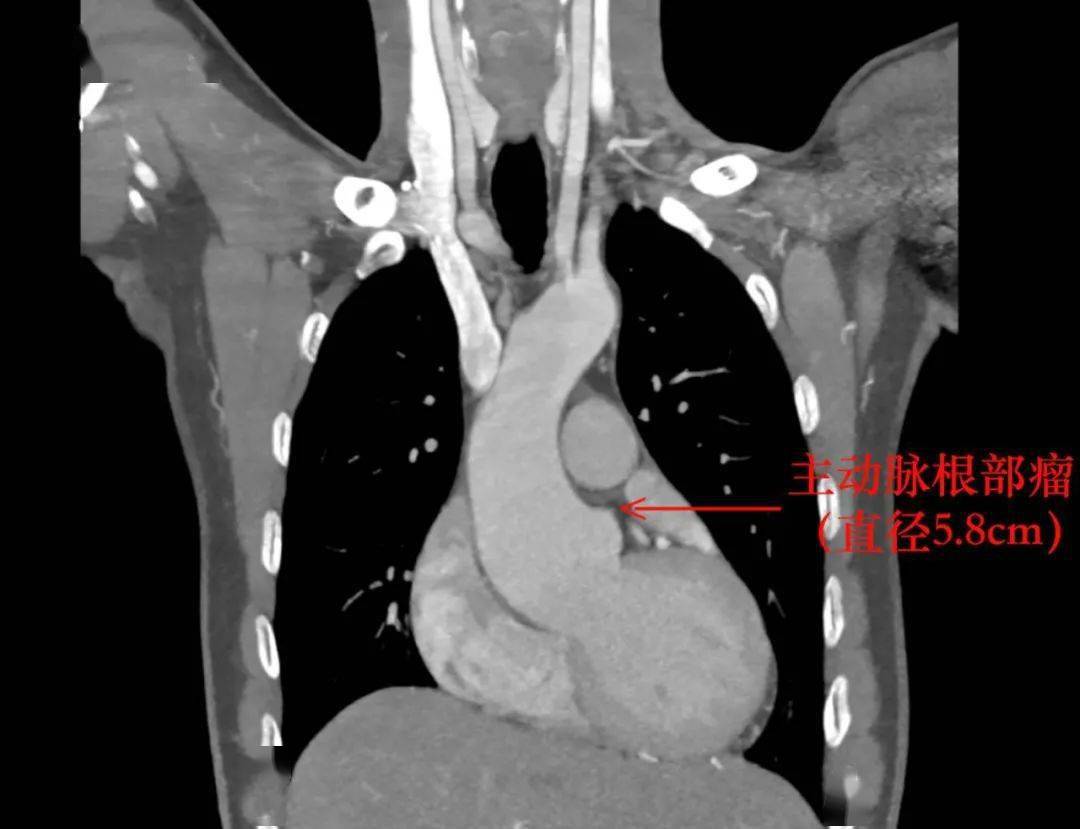

检查提示主动脉根部瘤

主动脉瓣中重度关闭不全

需外科手术治疗

8月13日 , 胡先生转入心胸血管外科 , 明确诊断为马凡氏综合征 。 由于胡先生 主动脉根部直径已达5.8cm , 出现主动脉破裂的风险极大 , 我院副院长、心胸血管外科主任陈鑫决定为其手术治疗 。